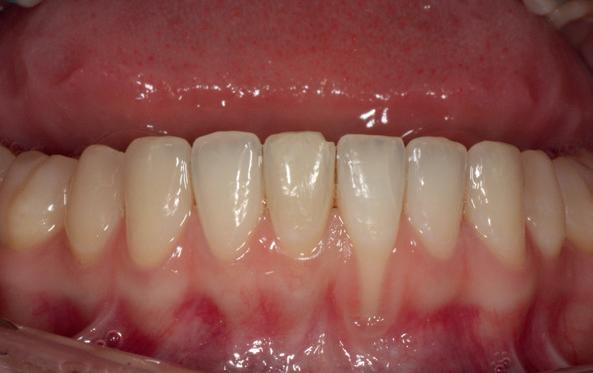

Na afronding van de eerste twee behandelstappen werd parodontale stabiliteit bereikt, zoals waarneembaar op de parodontiumstatus en (röntgen)foto’s (afbeelding 6, 8). De patiënt toonde aantoonbare verbetering in mondhygiëne (afbeelding 4) en bleef gemotiveerd om de behandeling voort te zetten.

3. Lichtfoto intake

4. Lichtfoto na infectie controle